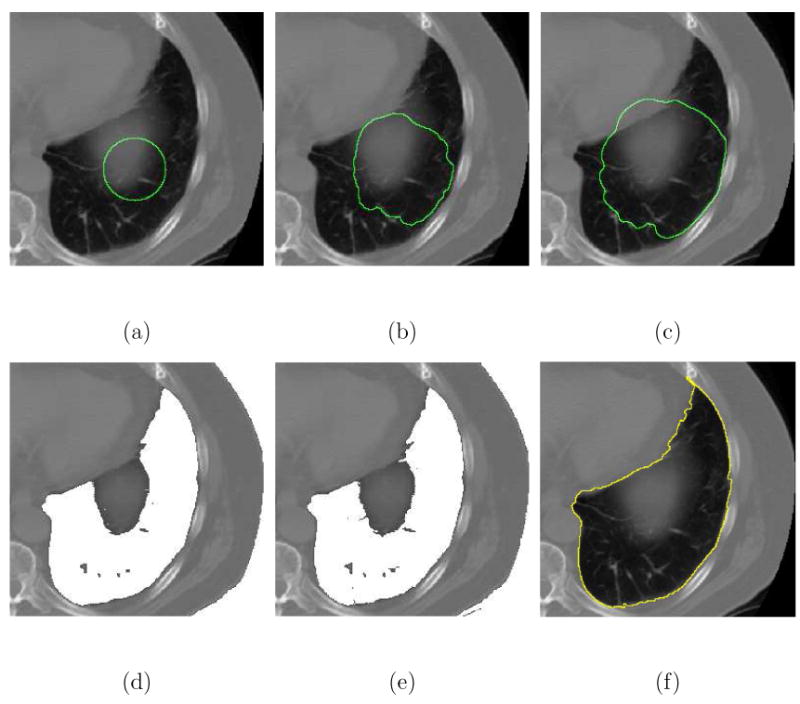

We conclude this section by illustrating the ability of the CFM algorithm to successfully segment difficult objects in pulmonary CT images. Figs. 14 and 15 show the results obtained using the Caselles-Malladi, Chan-Vese, and CFM methods for lung segmentation, which is required to identify the lung boundaries within the images. The lung in Fig. 14 has inner high intensity structures (some of which are connected to the lung boundaries) and the lung in Fig. 15 has blurred and ragged boundaries. The Caselles-Malladi contours were confined inside by the lung boundaries using a strong stopping force as depicted in Figs. 14(b) and 15(b). Using a slightly weaker stopping force resulted in leakage as respectively illustrated in Figs. 14(c) and 15(c).

Fig. 14.

Comparison of different segmentation techniques in extracting the lung in pulmonary CT images. (a) The initial contour. (b) The result (κc = −27.04%) of the Caselles-Malladi method using a strong stopping force. (c) The Caselles-Malladi contour leaked through the boundaries using a slightly weaker stopping force. (d) The result using the Chan-Vese method. Note that the background, whose intensity is similar to the lung, was also included as the ROI. (e) The result using a simple intensity thresholding. (f) The result using the CFM (β = 1.8) with κc = 98.99%.

Fig. 15.

Using different segmentation algorithms to segment the lung in pulmonary CT images. (a) The initial contour. (b) The result (κc = −50.61%) of the Caselles-Malladi method using a strong stopping force. (c) The Caselles-Malladi contour leaked past the boundaries using a slightly weaker stopping force. (d) The Chan-Vese method was unable to correctly capture the lung boundary. (e) The result using a simple intensity thresholding. (f) The result (κc = 98.02%) of the CFM using β = 1.8.

The Chan-Vese method failed to separate the lungs from the inner structures and the backgrounds as illustrated in Figs. 14(d) and 15(d). The images were incorrectly divided into two regions based upon the intensity values. The Chan-Vese algorithm also failed to exclude the blurred structure illustrated in Fig. 15(d) so that the lung boundaries were not correctly captured. The CFM algorithm successfully extracted the boundaries of the lungs while excluding inner structures and artifacts using a single initial contour with β = 1.8 as shown in Figs. 14(f) and 15(f). Finally, Table 2 summarizes the performance measures of the Caselles-Malladi and CFM methods, and Table 3 shows the approximate computation time using the CFM.